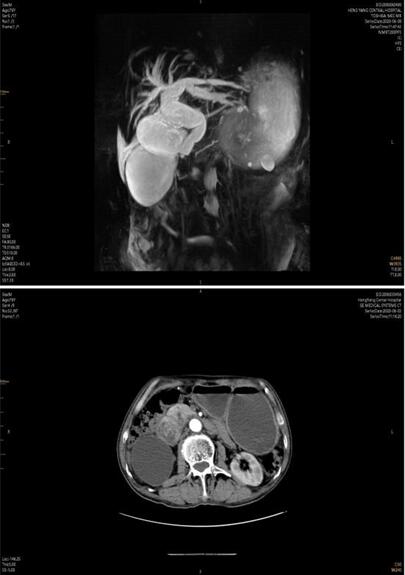

患者家屬經多方打聽,赴我院胃腸外科會診。譚曙光主任及賀賽奇副主任閱外院腹部CT片,考慮十二指腸惡性腫瘤合并梗阻可能性大,唯有手術治療方為解決患者病癥最好方式??紤]患者高齡,全身營養(yǎng)狀況差,脫水及貧血嚴重,予積極補液、維持水電解質平衡、腸外營養(yǎng)支持及輸血治療同時,完善術前相關輔助檢查。上腹部增強MRI+MRCP檢查提示:十二指腸水平段腫瘤,侵犯膽管下段、胰頭、橫結腸系膜,并周圍多發(fā)淋巴結腫大。十二指腸鏡下活檢病理:十二指腸粘膜慢性炎。

術前3天,患者并發(fā)上消化道出血,考慮腫瘤病變進展,侵及十二指腸局部血管出血,病情緊急,經采取措施積極控制出血及輸血治療后,譚曙光主任醫(yī)師主持科內疑難病例討論:患者為十二指腸腫瘤來源可能性大,瘤體大,分期晚,合并消化道梗阻及出血,手術指征明確及迫切。腫瘤侵犯膽管、胰頭、橫結腸系膜及血管,經典胰十二指腸切除即Whipple手術切除困難,需經十二指腸及胰腺后方血管入路(經腸系膜上動脈及腹主動脈、下腔靜脈表面)進行手術,難度極大,風險極高,隨時可能出現(xiàn)大血管破裂大出血并危及生命,為減輕患者創(chuàng)傷、術后恢復快,腹腔鏡手術操作更是難上加難。